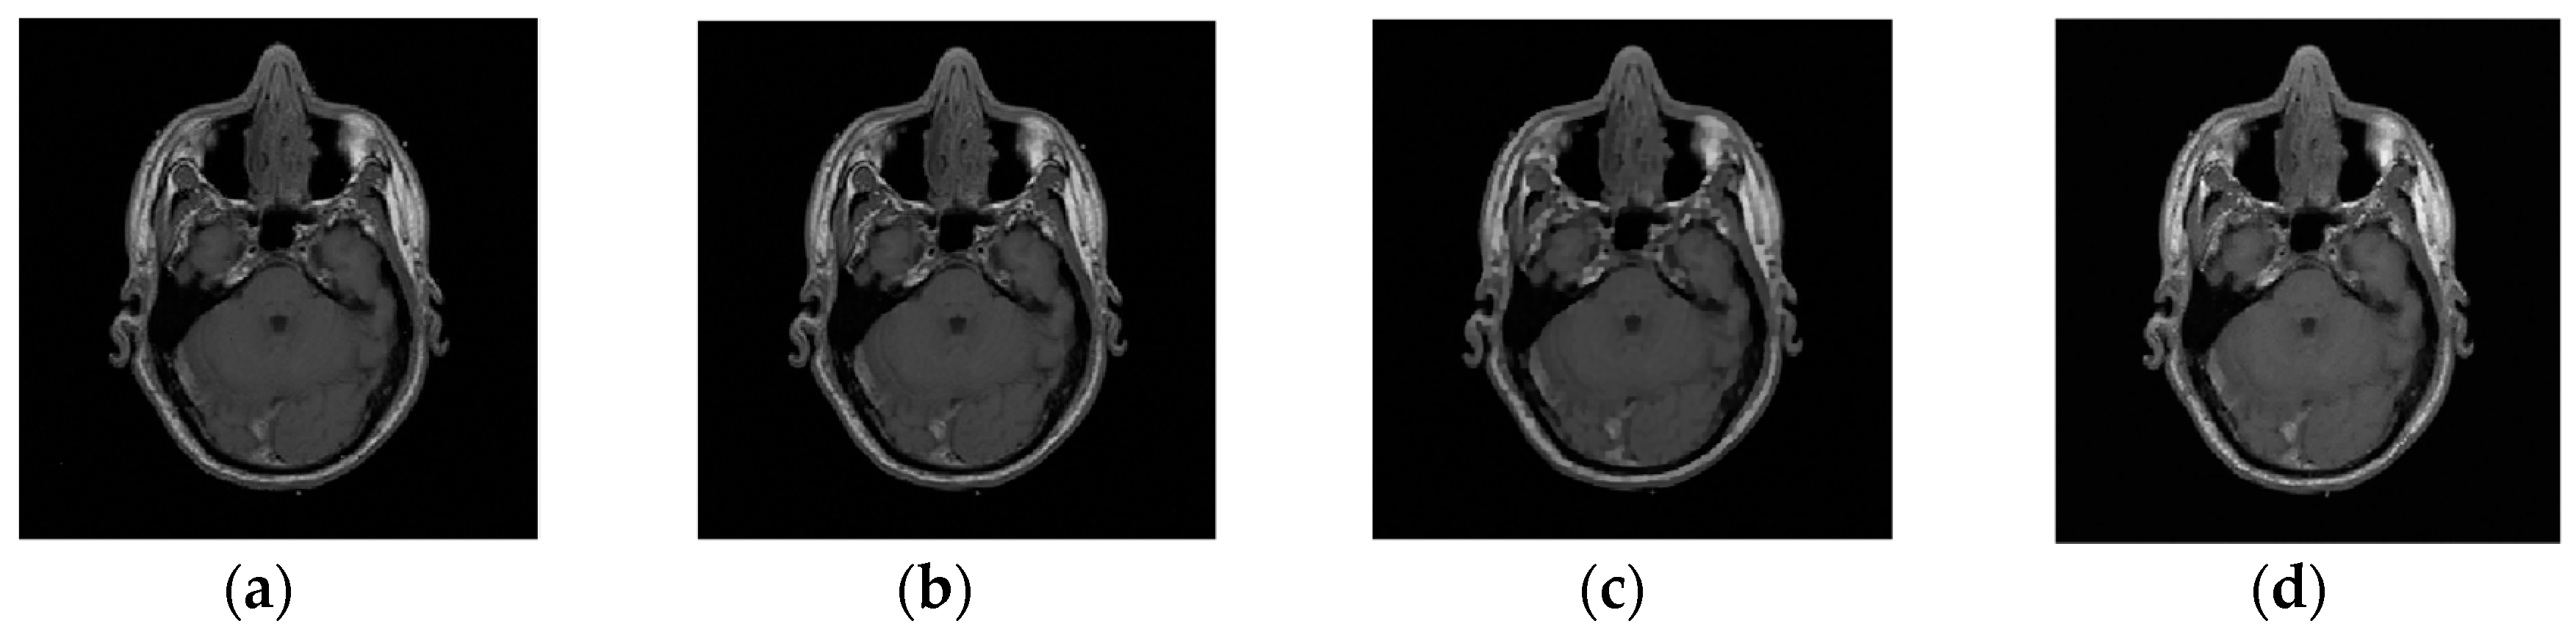

Example 2: In this example, the reconstruction efficiency is tested for the MRI image. Unlike the 1D case, the MRI image can be successfully recovered with almost all implemented algorithms. The percentage of missing samples is considered to be around 45. The original and image with missing samples are shown in Figure 6. The reconstruction procedures show that the radial-Fourier provided the best PSNR. However, the processing time is the longest using the radial-Fourier approach. The reconstruction results are shown in Table 1 and Figure 7.

Figure 7. Reconstruction results for the magnetic resonance imaging (MRI) image, considering 45% the missing information; the results are obtained using the (a) gradient; (b) radial-Fourier; (c) TV-min-DCT; and (d) Douglas–Rachford algorithms.

Table 1. The PSNR and reconstruction time for different algorithms. TV, total variation; DCT, discrete cosine transform.

AlgorithmPercentage of Missing PixelsReconstruction Time (sec)PSNR [dB]

Gradient45%11.430.5

Radial-Fourier43%120.147.8

TV-min-DCT45%0.943.9

Douglas–Rachford45%11.231.5